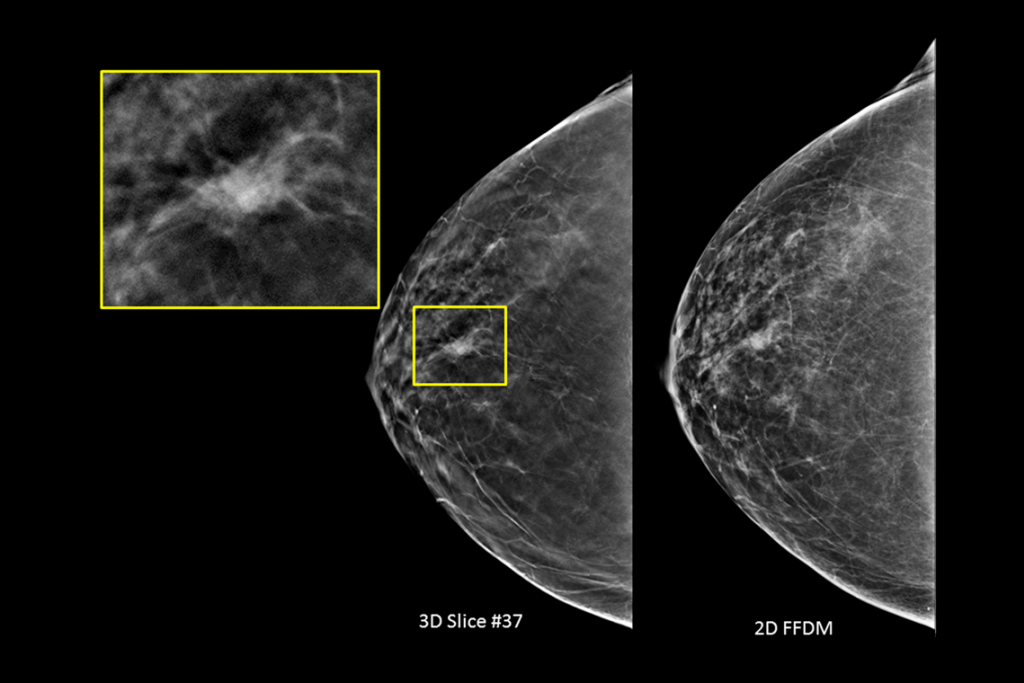

Imagens clínicas de mamografia com lesão suspeita